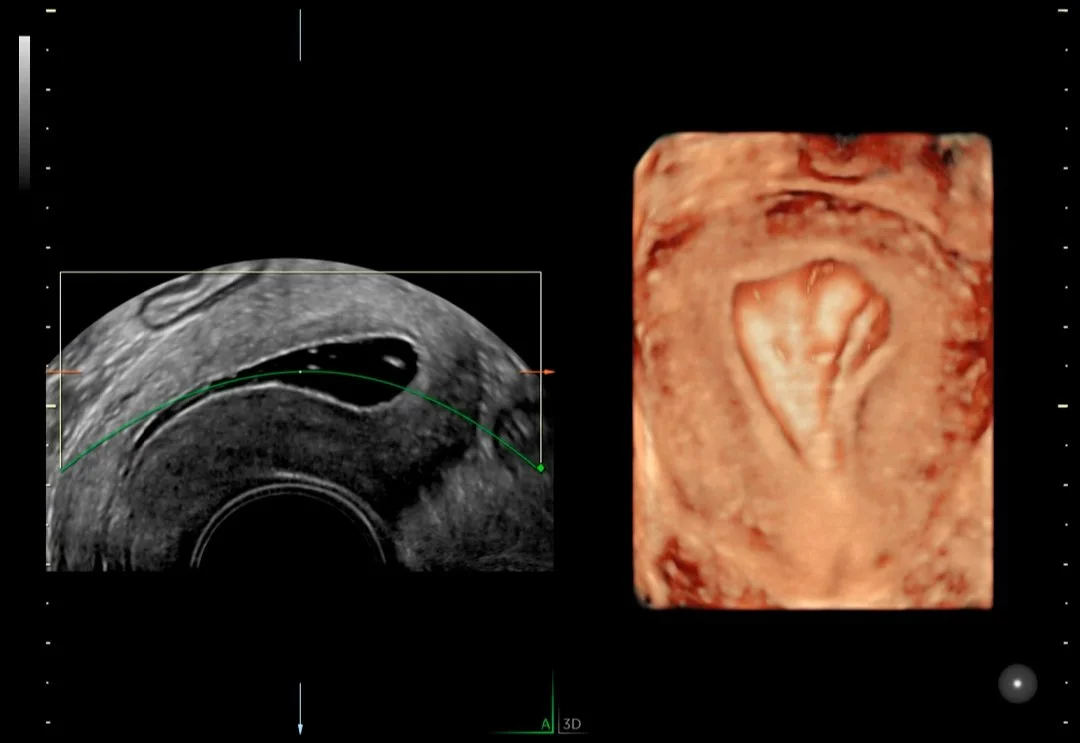

Ginecología

A menudo, la ecografía es la primera línea de defensa para diagnosticar afecciones ginecológicas. El dolor pélvico, el sangrado postmenopáusico, la disfunción genitourinaria y la infertilidad pueden ser síntomas confusos y preocupantes para sus pacientes. Necesitan respuestas y confían en su experiencia para obtener un diagnóstico y tratamiento precisos.

Medicina reproductiva asistida

Entendemos el impacto que tiene la infertilidad en la vida de sus pacientes y en su práctica. Por este motivo, los sistemas de ultrasonidos Voluson superan continuamente los límites de la adquisición de imágenes para ofrecerle herramientas sencillas e innovadoras que le ayuden a usted y a sus pacientes a vivir el sueño de un embarazo próspero.